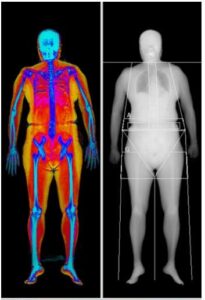

▎案例分享─全身身體組成成份(含肌肉質量)分析

根據2019年亞洲肌少症共識會(AWGS)對於肌少症的診斷,利用DXA測量四肢骨骼肌肉質量指數(ASMI):男<7.0 kg/m2、女<5.4 kg/m2 為標準。內臟脂肪(VAT):<100 cm2為正常,100-160 cm2為代謝症候群風險增加族群,>160 cm2為高風險族群。

肌少症及代謝症候群高風險族群

65歲女性

身高          157.6cm

體重           60.9kg

體脂率          42.4%

BMI          24.5 kg/m2

內臟脂肪VAT  163 cm2

(代謝症候群高風險)

骨骼肌肉質量指數ASMI   5.15 kg/m2

(肌肉質量不足)